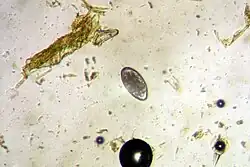

Vajíčko H. contortus

Červi H. contortus jsou nitkovitého tvaru, samci měří 10–20 mm, samice 18–30 mm. Na předním konci je rudimentární ústní kapsula, jež obsahuje kyjovitý zub, pomocí něhož paraziti narušují cévy. Obě pohlaví mají v hlavovém konci vystupující cervikální papily. Samci mají silně vyvinutou bursu copulatrix. Spikuly samců (při kopulaci se zasouvají do pohlavního otvoru samiček) jsou krátké (0,460-0,506 mm), masivní a na konci nitkovité. Samice mají vulvu v kaudální části těla a je překryta chlopní. Vajíčka měří 70–85 x 41 μm a obsahují 16–32 blastomer.[2]